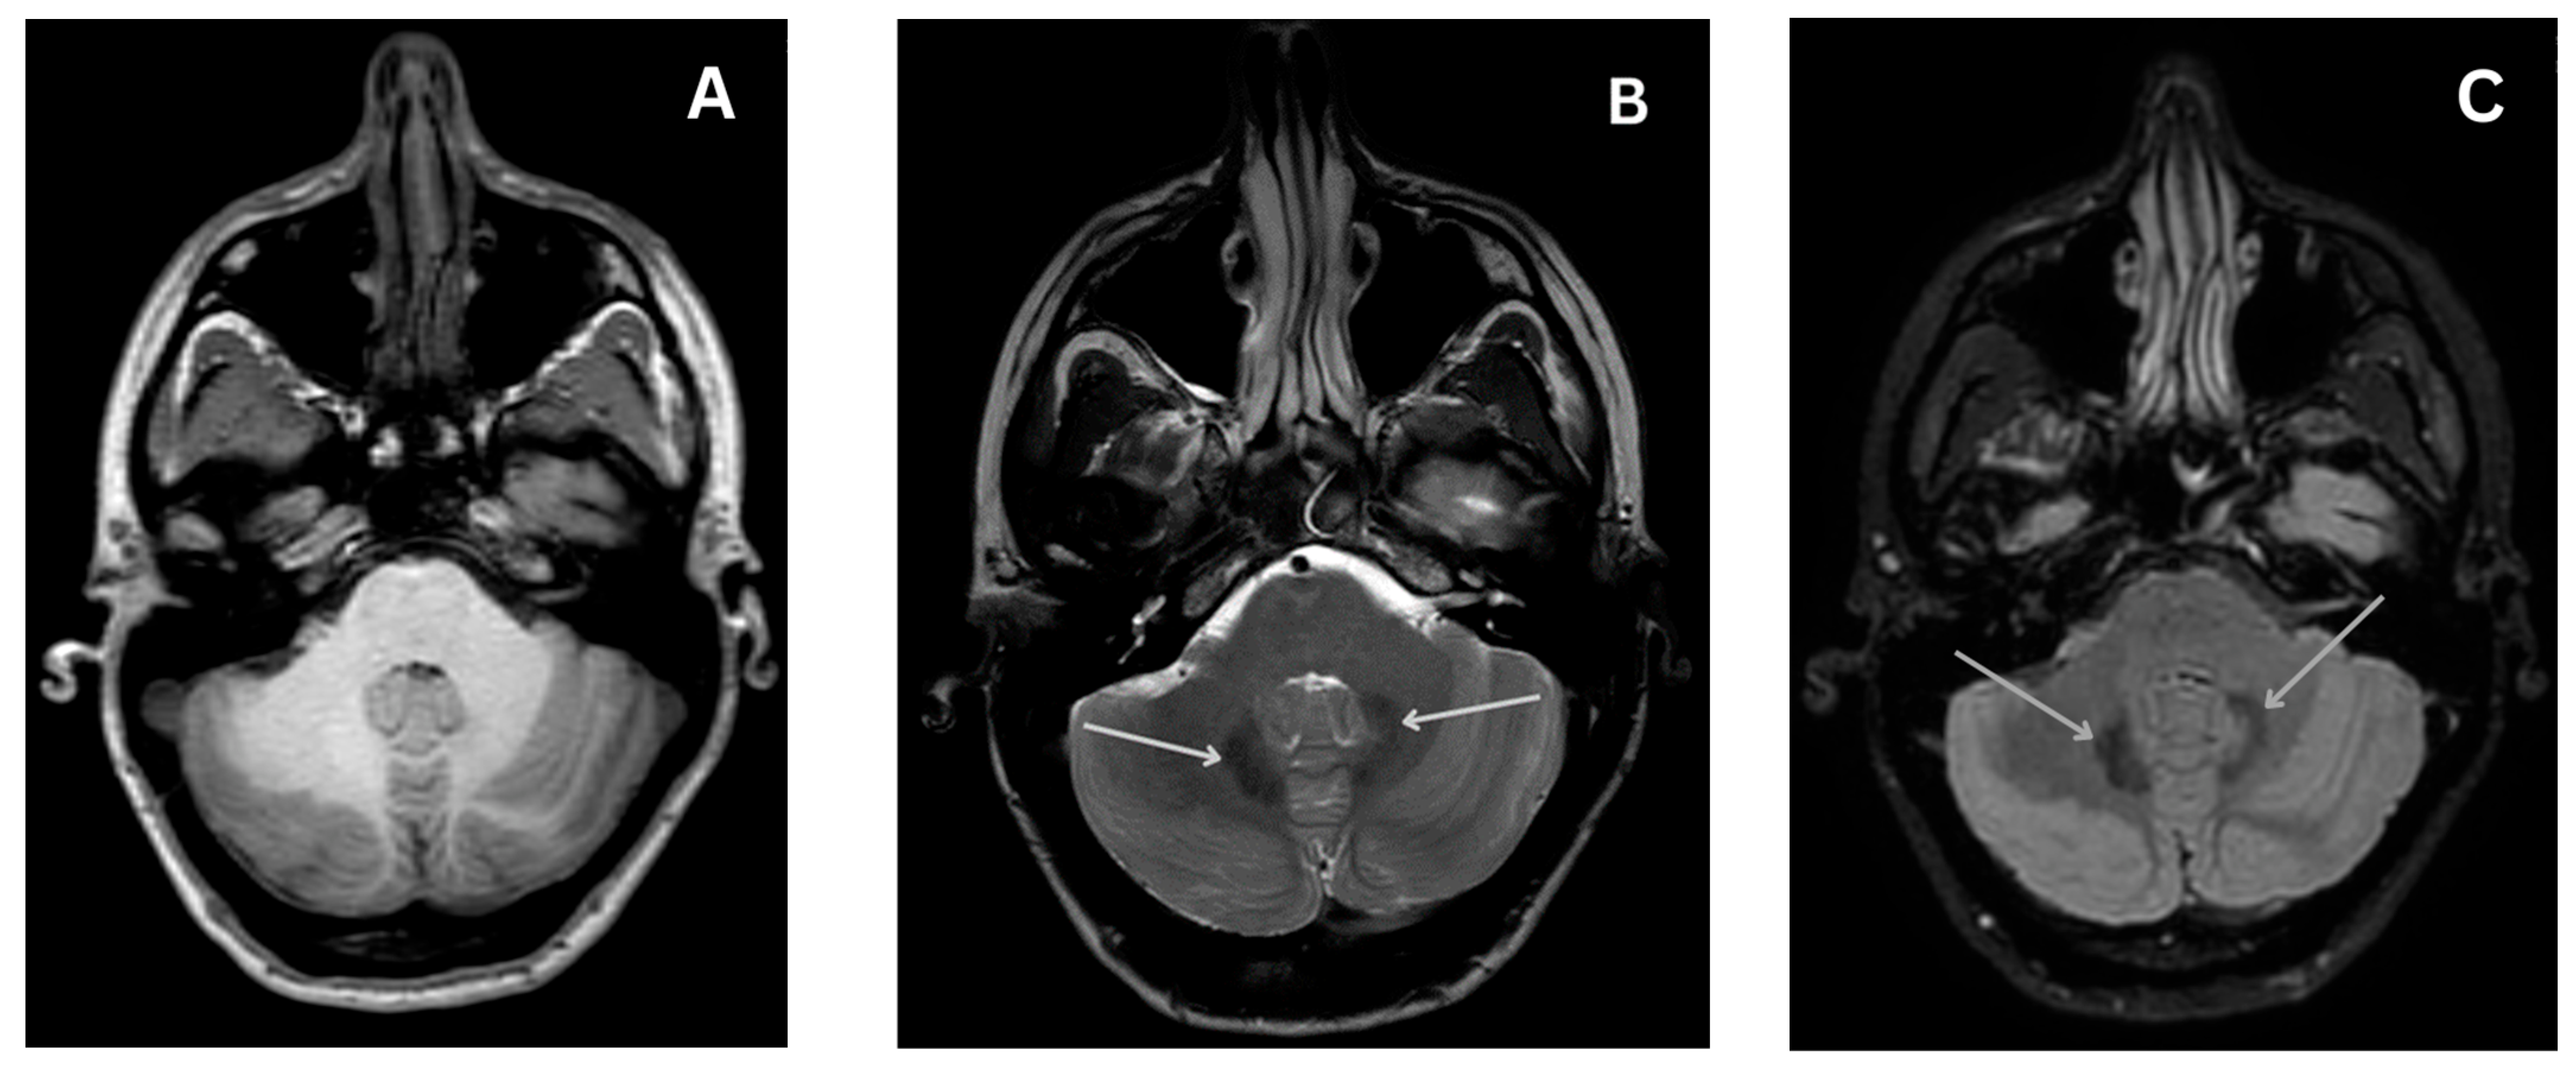

4.4.4. Magnetic Resonance Imaging